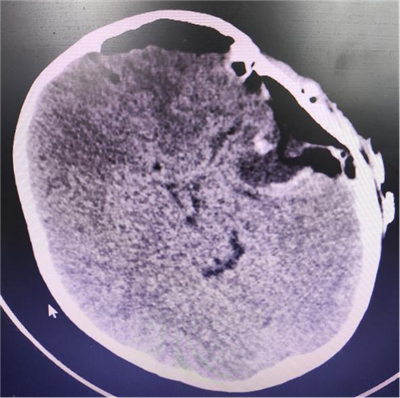

随即10岁小强入住我院神经外科,住院医师对其完善了相关检查,头颅磁共振平扫+增强检查提示其左侧颞部颅板下见大小约54*43毫米异常信号,周围脑组织受压明显,诊断其为脑膜瘤。

术前